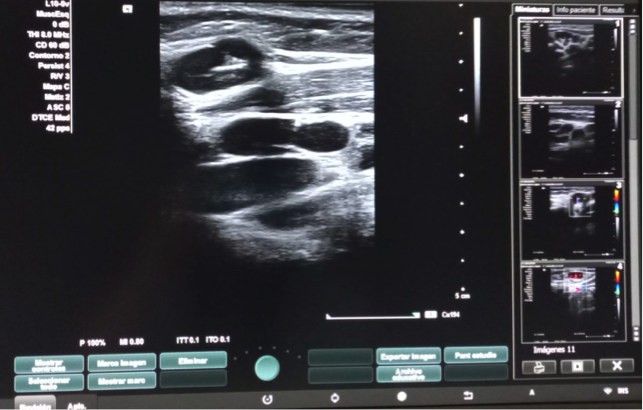

Hallazgos ecográficos

Dos adenopatías en territorio laterocervical derecho, con hilio central y doppler positivo, alguna con diámetro transversal superior al longitudinal, de probable origen reactivo y una adenopatía supraclavicular sin hilio central y con vascularización generalizada.